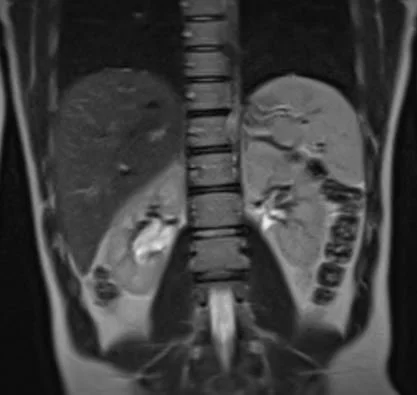

Rare and pediatric disease trials come with complex challenges that require specific expertise and experience. We have the radiology exerts to support the specific requirements of pediatric clinical trials. Many rare diseases affect children, and pediatric trials bring additional challenges.

They require specific protocols, involve additional regulations and demand expertise and experience. BICL’s experts are experienced in oncology, MSK and other pediatric disorders including growth plate disturbance, bone age and osteochondroma.